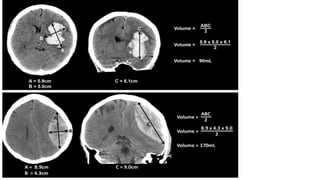

VOLUMEN DEL SANGRADO

• Predictor de mortalidad 30d > 60cm3

• Metodo ABC/2

• A = El mayor dm del hematoma

• B = dm medido a 90 grados hacia A.

• C = Número aproximado de cortes

que contienen el hematoma

multiplicado por el grosor del corte.

DOI: 10.1594/ranzcr2014/R-0129